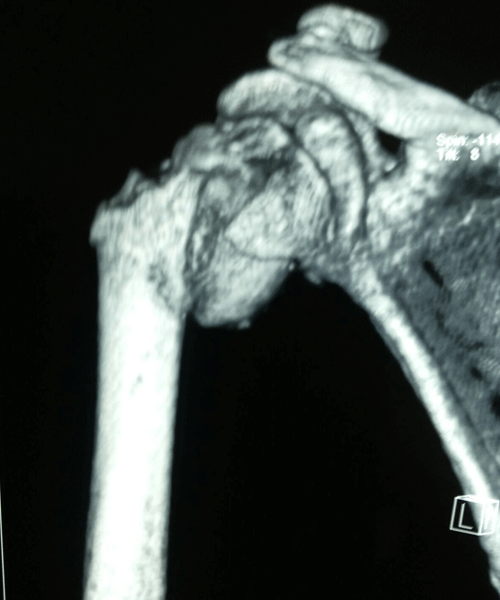

Case:18 Comminuted Fracture Upper Humerus

Female 65 years sustained fall in the house had displaced fracture of head of left Humerus with displaced fragment of greater tuberosity was treated with open deduction and philos plate fixation.

Pre-Op-Xray

Pre-Op CT Scan

CT Scan lateral

Post-Op Xray